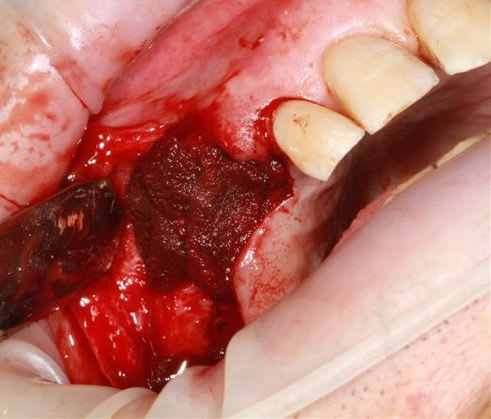

Ensuite zone 16 .. carottage, sciage en vest, carottage prélèvement de la carotte ajustage (délicat ça glisse:-)))

modelage zone 13,finitions, mise en place du bloc osseux, qui sera soigneusement impacté (pas de vis) prélèvement d'un petit bloc triangulaire pour finir la fermeture, éponges de gelatemp, sutures.